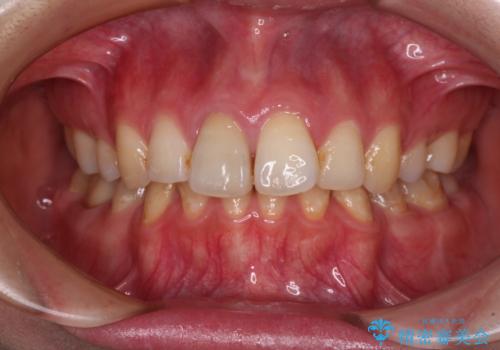

- 左下欠損部のインプラント治療と、右下の歯の痛みを気にして来院された患者様です。

左下の欠損部は、世界中で高い信頼を得ているストローマンインプラントを用いて治療を行うこととしました。

ただし、長期間欠損を放置していたことで、咬み合う上の奥歯が動いてしまっていたので、まずは上顎奥歯の部分矯正を行い、より理想的な咬み合わせを目指すこととしました。

まず生活歯髄療法を行い、その後部分矯正やインプラント処置を行いましたが、最初の処置から1年以上経っても右下奥の処置歯の神経組織に異常は認められませんでした。

部分矯正を行ったことで、違和感のない咬み合わせを達成することができました。